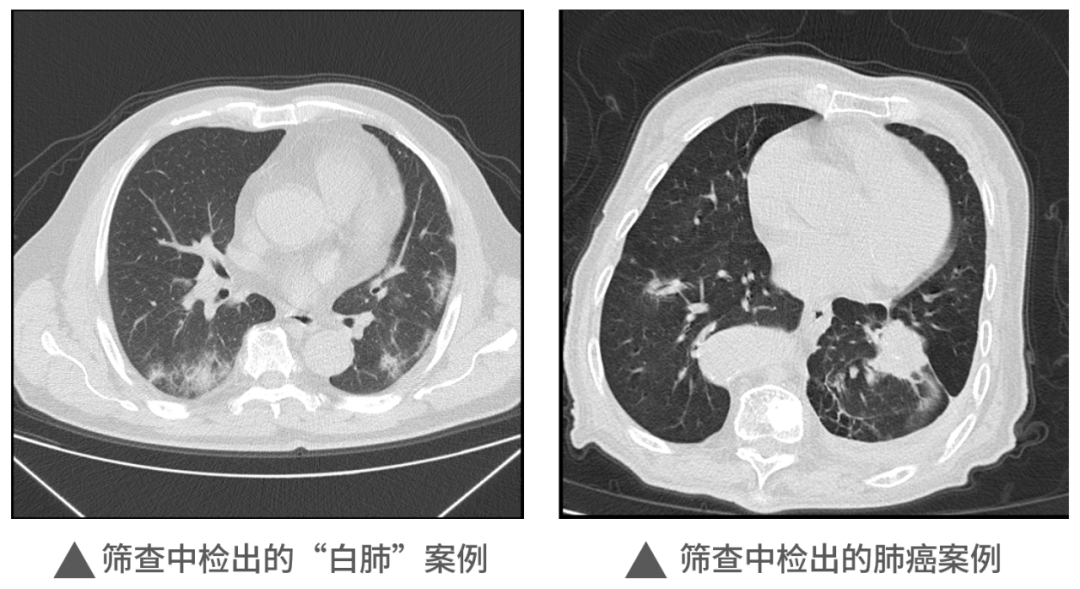

本次活動(dòng)中,明峰醫(yī)療移動(dòng)CT充分展現(xiàn)了它的適應(yīng)性和便利性,在近1000人的檢查中,共查出肺部炎癥300余例,肺部結(jié)節(jié)560例,同時(shí)檢出一例肺癌病例。這對(duì)于本次篩查人員今后胸部健康和治療提供了重要的參考和指導(dǎo),為全區(qū)居民和企業(yè)提供了堅(jiān)實(shí)的保障,同時(shí)大大提升區(qū)內(nèi)的醫(yī)療健康保障能力。未來,明峰醫(yī)療醫(yī)療仍將持續(xù)致力于高端醫(yī)療設(shè)備的普惠應(yīng)用。作為杭州市錢塘區(qū)的區(qū)內(nèi)企業(yè),將沿著區(qū)委區(qū)政府“四個(gè)全域”建設(shè)的發(fā)展規(guī)劃和區(qū)衛(wèi)健系統(tǒng)提出的目標(biāo)及要求,發(fā)揮人才企業(yè)的優(yōu)勢,以科技創(chuàng)新引領(lǐng)企業(yè)發(fā)展,為區(qū)內(nèi)產(chǎn)城融合的服務(wù)配套做好應(yīng)有的保障和支撐工作,探索政產(chǎn)學(xué)研合作的新思路新模式,共建共享,共同成長,造福更多的人民百姓,在書寫中國式現(xiàn)代化的錢塘答卷上也添上濃墨重彩的一筆。